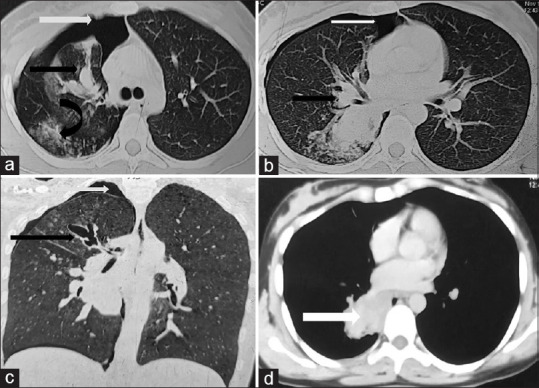

Abstract: In patients with severe asthma with allergic bronchopulmonary aspergillosis (ABPA), a variety of radiological manifestations are seen. Pleural involvement is rare, and a very few case reports of secondary spontaneous pneumothorax have been reported in the literature. Here, we report an even rarer case of secondary spontaneous pneumothorax in a patient of ABPA 'without asthma'.